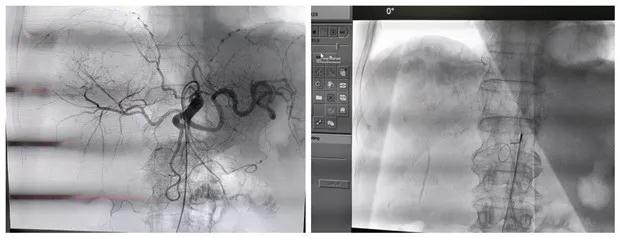

患者男性,69岁,因“右胁部胀痛伴乏力3月,发现肝占位2天”。入院行MRI检查提示:右肾癌并出血,肝内及腹膜后淋巴结多发转移。与彩超室韩娟娟主治医师配合行彩超引导下肝脏肿瘤穿刺术,取病理示:查见低分化腺癌,倾向于透明细胞型。

明确诊断后,经科室讨论考虑,患者为肿瘤晚期,失去外科手术机会,经肝动脉及肾动脉栓塞化疗是目前治疗不能手术切除肿瘤的最好治疗方法。经与患方充分沟通后,给予行肝动脉及右肾动脉栓塞化疗术,手术顺利,术后患者恢复良好。

经动脉栓塞是阻断肿瘤的供血动脉,切断肿瘤细胞的营养供应,达到饿死肿瘤细胞的目的;同时给予肿瘤供血动脉灌注化疗,化疗药物浓度高,是常规静脉化疗药物浓度的1000倍,可有效杀死肿瘤细胞。